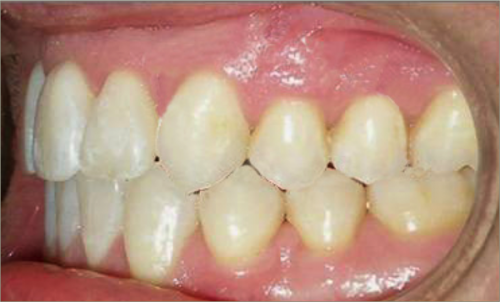

30 year old male:

Diagnosis:

- Upper and lower crowding

- Narrow upper & lowerarch forms

- Open bite

Treatment:

- Invisalign

- Non-Extraction

- 27 months